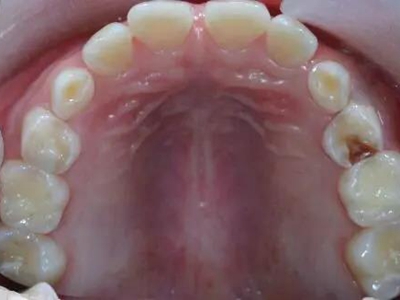

酸蚀症牙齿内侧有大片黄斑图

酸蚀症患者的牙齿内侧可出现大片黄斑,境界不清晰,深浅不均匀,呈淡黄色至黄褐色,牙齿骨质尚未出现缺损,需控制进食酸性食物,并治疗胃部疾病。